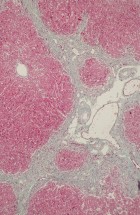

The Department’s main activities encompass research and specialized tasks. It focuses on clinical, pathoanatomical, pathohistological, immunohistochemical, and molecular diagnostics of diseases in both domestic and wild animals, including reproductive pathology. Operations within the department are structured around fieldwork and laboratory analyses.

- Performing pathohistological, cytological, immunohistochemical, and molecular diagnostics.